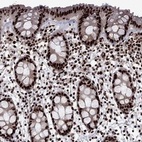

Immunohistochemical staining of human rectum shows strong nuclear positivity in glandular cells.